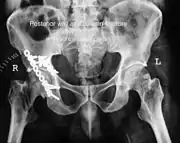

Anterior wall fracture

As seen on 3D CT image

Fixation with screws and plate